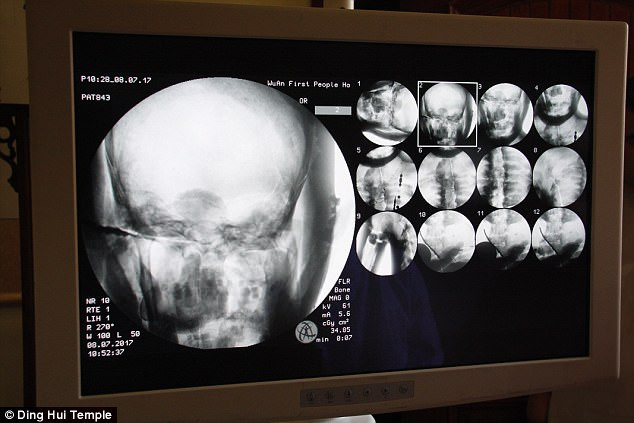

Các chuyên gia tiến hành chụp cắt lớp vi tính xác ướp đại sư Từ Hiền trước sự chứng kiến của các nhà sư, phật tử và phương tiện truyền thông.

Những người có mặt tại sự kiện trên đều vô cùng bất ngờ khi các chuyên gia thông báo thi hài đại sư Từ Hiền vẫn còn đầy đủ xương và sọ não hoàn chỉnh.

"Chúng ta có thể trông thấy xương cốt đại sư vẫn còn chắc khỏe như xương của người thường", bác sĩ Wu Yongqing chia sẻ.

Theo bác sĩ Wu Yongqing, xương hàm trên, hàm dưới, xương sườn, cột sống và tất cả khớp đều hoàn chỉnh. Điều này thật đáng kinh ngạc.